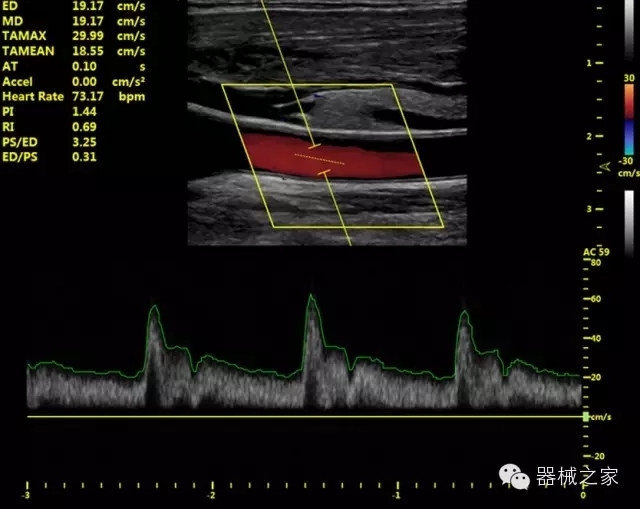

臨床圖片賞析

·獨有的HoloTM PW 實時3取樣門PW成像技術(shù),精確進行血管診斷;

·一鍵優(yōu)化B、Color、PW,Auto Doppler自動識別血管位置、偏轉(zhuǎn)角度等,提高工作效率;

·30°超廣角精細偏轉(zhuǎn)成像技術(shù),更優(yōu)異的頻譜圖像;